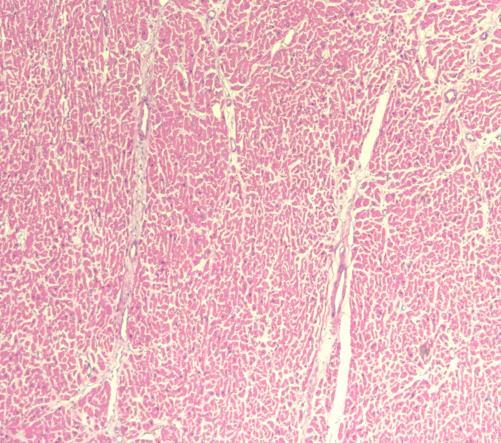

冠脉情况 心肌镜下情况

窦房结镜下情况

房室结镜下情况